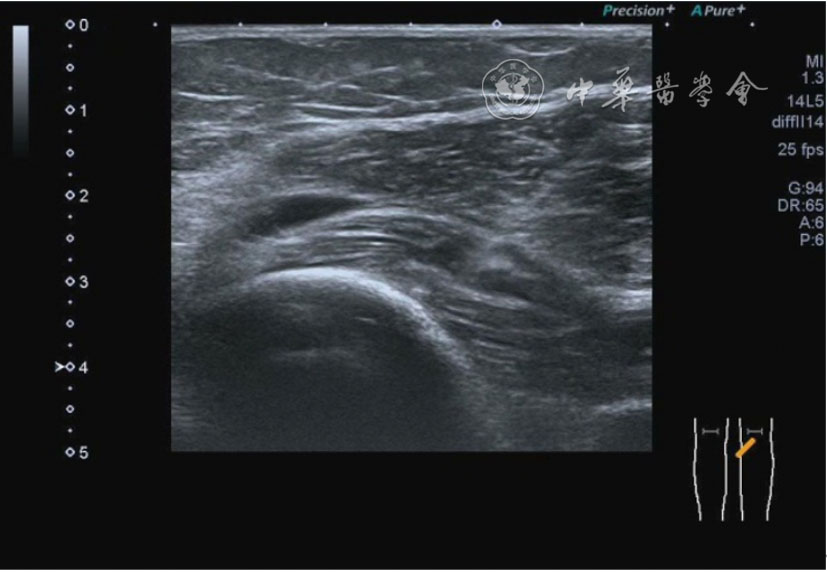

2.膝关节静态结构治疗。动力平衡失调后,继发静态结构变化,出现内外侧副韧带、交叉韧带、脂肪垫、半月板等结构变化。这里介绍半月板与交叉韧带的处理。(1)膝关节静态结构半月板治疗。在膝关节骨关节炎中主要是突出和损伤。突出主要发生于膝内翻引起的内侧半月板突出,引起内侧副韧带的张力增高。内侧半月板与内侧副韧带相连,是引起膝关节内侧疼痛的主要原因之一。治疗主要是针刀剥离松解,部分损伤可行PRP注射。①半月板突出针刀剥离松解治疗。针刀治疗主要是松解和减压,缓解疼痛,不能复位。以内侧半月板突出治疗为例。患者平卧位,髋轻度外展外旋,膝关节屈曲30°,膝下垫一软枕。选用10 MHz超声探头,穿刺区域常规消毒,探头涂抹耦合剂后套入无菌手套碘伏消毒或使用无菌耦合剂。将探头置于患者皮肤表面,内侧关节间隙长轴扫查,找到半月板突出最高点,用25G针头,抽吸1%利多卡因3 ml逐层麻醉直到半月板。选用直径1 mm的Ⅰ型2号针刀从头侧向足侧方向在内侧副韧带与半月板之间,以及半月板内部进行剥离松解3~5刀拔出针刀(图13),局部压迫5分钟,无菌敷料覆盖。②半月板损伤PRP注射治疗。半月板损伤主要表现为髌下痛,伸膝加重,查体在髌下髌韧带与侧副韧带之间,沿关节间隙有固定或局限性压痛,伸膝过程中尤为明显。MRI可示半月板断裂、损伤。如果出现绞索,严重影响功能需手术治疗。半月板损伤治疗,以注射PRP修复为主。以内侧半月板后角损伤为例。患者俯卧位,治疗前准备同半月板突出针刀剥离松解治疗。选用25G注射针头,抽取1%利多卡因2 ml局部麻醉后,制取1.5 ml PRP,穿刺到达半月板撕裂处注射,注射完毕后出针(图14),局部压迫2分钟,无菌敷料覆盖。(2)膝关节静态结构交叉韧带治疗。膝关节骨关节炎交叉韧带损伤多为部分损伤,治疗早期主要为药物或PRP注射,效果不佳时针刀做止点松解。①后交叉韧带损伤药物注射治疗。主要治疗韧带肿胀、无明显断裂患者。患者俯卧位,膝关节伸直位。一般选用10 MHz超声探头,治疗前准备同半月板突出针刀剥离松解治疗。将探头置于患者皮肤表面,后交叉韧带长轴扫查,找到胫骨止点,选用22G长针头,抽吸1%利多卡因3 ml+曲安奈德10 mg,从头侧向足侧方向穿刺到后交叉韧带胫骨止点部位的韧带表面进行注射,注射结束拔出针头(图15),局部压迫2分钟,无菌敷料覆盖。②前交叉韧带损伤PRP注射治疗。患者仰卧位,膝关节伸直。选用10 MHz超声探头,治疗前准备同半月板突出针刀剥离松解治疗。将探头置于患者皮肤表面,短轴扫查,找到前交叉韧带胫骨止点,选用25G针头,抽吸1%利多卡因3 ml逐层麻醉直到韧带止点部位,制备PRP 3 ml注射到前交叉韧带显露部位,注射结束拔出针头(图16),局部压迫2分钟,无菌敷料覆盖。③前交叉韧带损伤针刀剥离松解治疗。体位与治疗前准备同前交叉韧带损伤PRP注射治疗。短轴扫查找到前交叉韧带胫骨止点,选用25G针头,抽吸1%利多卡因3 ml逐层麻醉直到韧带止点部位,选用直径0.6 mm的Ⅰ型2号针刀从外侧向内侧于前交叉韧带胫骨止点部位剥离松解3~5刀拔出针刀(图17),局部压迫5分钟,无菌敷料覆盖。

图16 超声引导下前交叉韧带损伤富血小板血浆注射治疗